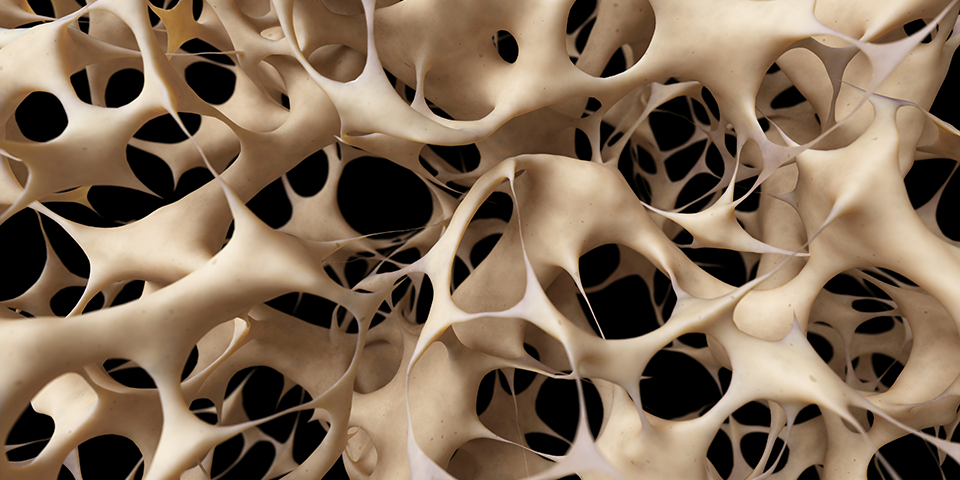

Cum se poate dezvolta osteoporoza în oase

Pentru a putea vorbi de cauze trebuie să înțelegem cu funcționează exact acest sistem de osificare. Organismul de când este copil până la maturitate, undeva în jurul vârstei de 20 de ani, transformă țesutul cartilaginos în țesut osos. Astfel oasele sunt mai dense și puternice, capabile de a desfășura diverse activități fără probleme.

La nivelul osului se găsesc 2 celule cu funcții foarte importante, una dintre acestea este responsabilă de folosirea mineralelor din corp cu scopul de a forma structuri osoase, iar cealaltă are misiunea de a distruge țesutul osos învechit, eliberând astfel mineralele în sânge.

Undeva pe la vârsta de 35 de ani, acest proces își pierde ușor și foarte lent din randament. Oasele persoanelor mai în vârstă fiind mai predispuse la fracturi decât oasele unei persoane tinere. Această acțiune este normală pentru toți oamenii, iar în cazul osteoporozei are loc același proces, dar mai rapid.

Osteoporoza poate fi cauzată de către mineralizări accentuate